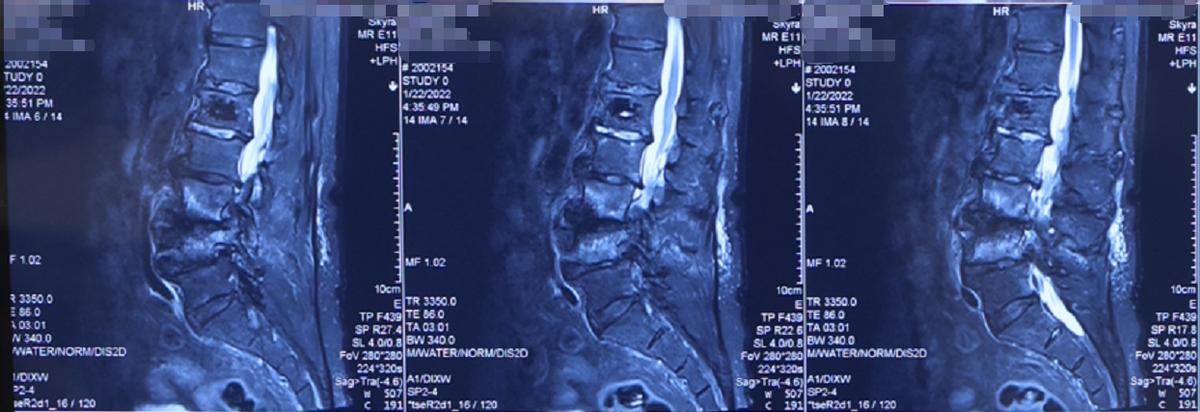

我们知道,随着年龄的增加,人体的各项机能和器官、组织会随之老化,腰椎也是如此。许多大家熟知的腰椎疾病,比如腰椎间盘突出症、腰椎管狭窄症、腰椎滑脱、腰椎退行性侧弯等,也都是腰椎退行性疾病。只要人到了一定的年龄,腰椎就会出现老化、退变的趋势,那如果人到了90岁,或者90岁以上,他们的腰椎又会是怎么样的状态?

近日,我就接诊了一位90岁高龄的老年患者,他的腰椎出现了退变性脊柱侧弯。虽然他不能代表所有老年人的腰椎情况,但是像他这样出现这类腰椎退变性侧弯的老年人还真不少,需要老年人和家属们引起警惕。